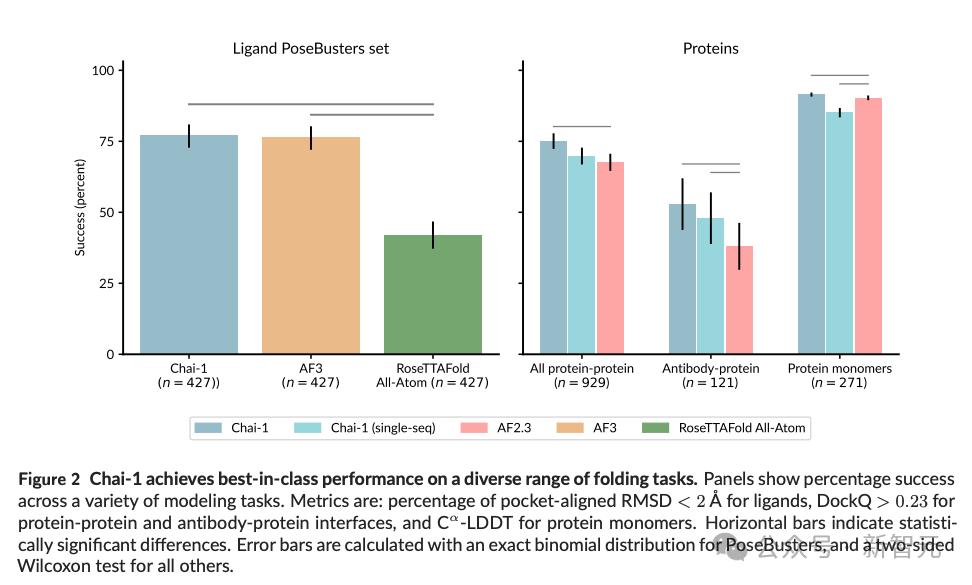

根据DockQ上的可接受预测率基准,Chai-1能比基于MSA的AlphaFold-Multimer模型(67.7%) 更准确地折叠多聚体 (69.8%)。

这个结果,让Chai-1成为第一个仅使用单序列信息、无需MSA搜索,就能以AlphaFold-Multimer水平预测多聚体结构的模型。

在PoseBusters基准上,仅给出蛋白质序列和配体化学成分的信息时,Chai-1对配体预测结果的RMSD(均方根偏差)成功率为77%,超过了AF3的76%。